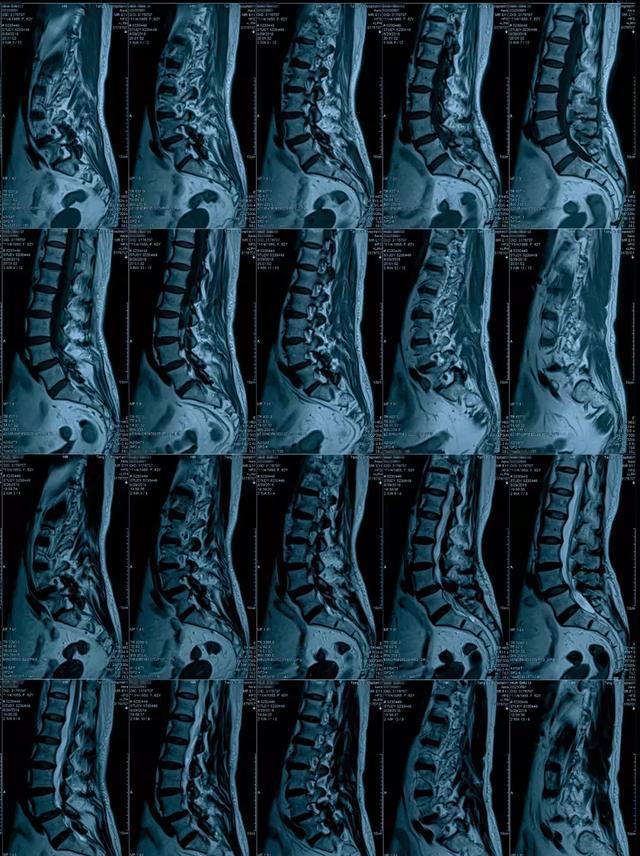

术前影像学检查:腰椎滑脱病人,l4/5的一个退变型滑脱,这个病人的主要